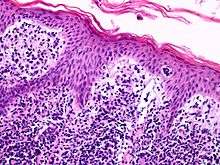

![]() A histological view of Lutzner cells surrounded by erythrocytes in a blood smear. | |

Lutzner cells were discovered by Marvin A. Lutzner, Lucien-Marie Pautrier, and Albert Sézary. These cells are also referred to as Pautrier’s abscess, Sézary’s cell, or Sézary-Lutzner cells. They are a form of T-lymphocytes that has been mutated[1] This atypical form of T-lymphocytes contains T-cell receptors on the surface and is found in both the dermis and epidermis layers of the skin. Since Lutzner cells are a mutated form of T-lymphocytes, they develop in bone marrow and are transported to the thymus is order to mature.[2] The production and maturation stages occur before the cell has developed a mutation. Lutzner cells can form cutaneous T-cell lymphoma, which is a form of skin cancer.[3]